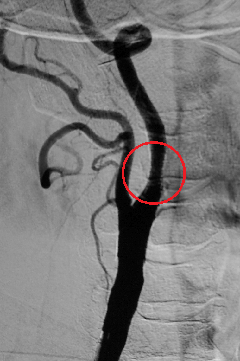

(下図)内頸動脈狭窄症に対して頸動脈ステント留置術を施行しました。良好な拡張が得られています。

頸動脈狭窄症、〇が狭窄している部分

頸動脈ステント留置術後